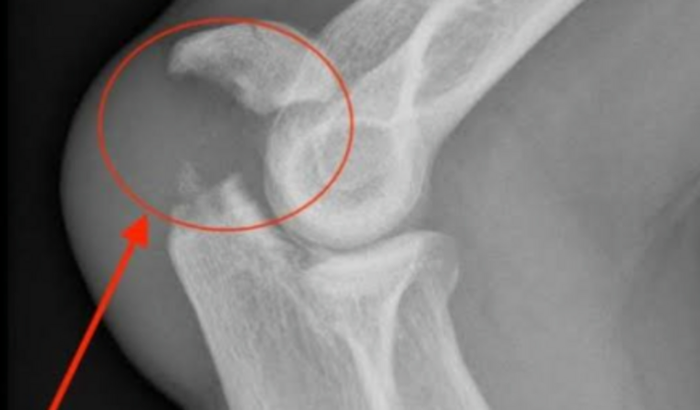

Acidente de moto fratura na ponta da rádio.. Preciso de ajuda tenho 3 filho 1 recém nacido

Sou motoboy sofri um acidente de moto,  dia 10/02/2023 estou aguardando cirurgia tenho 3 filhos 1 recém nascido estou impossibilitado de trabalho agradeço muito de coração obrigado 🙏 ver tudo

Sou motoboy sofri um acidente de moto,  dia 10/02/2023 estou aguardando cirurgia tenho 3 filhos 1 recém nascido estou impossibilitado de trabalho agradeço muito de coração obrigado 🙏